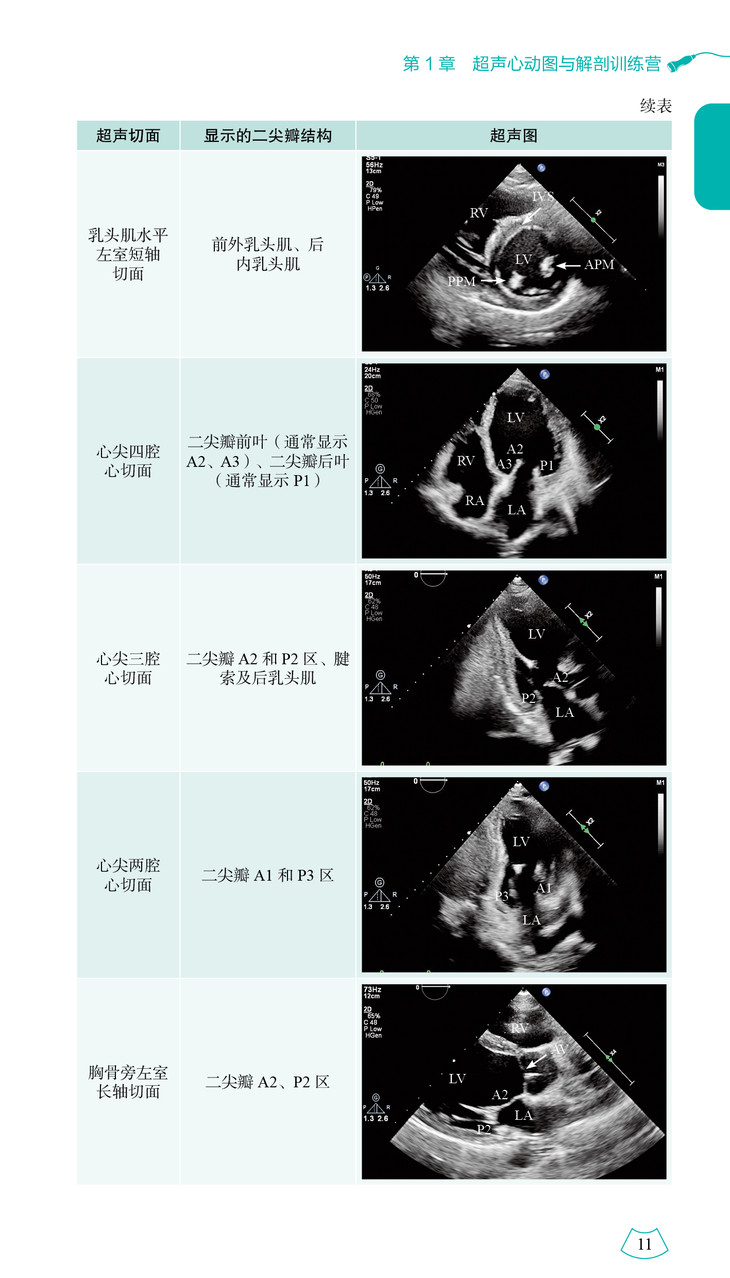

本书详尽阐述了心脏的解剖结构并配以对应的超声图像,从疾病的病理生理出发,分析心脏的结构和功能改变,将解剖结构、血流动力学变化与临床和超声表现融为一体,以示意图、表格的形式进行总结和升华,方便读者进一步理解、掌握各类心血管疾病的诊断及鉴别诊断。基于超声医师兼顾临床及科研工作的情况,本书采用 “训练营”的形式,通过教学视频、超声人体模型及超声演示等对心血管的解剖结构和各种超声技术进行介绍,并设定具体的临床背景进行实战演练,以通俗形象的语言讲解心脏疾病的超声诊断思路。

本书参考超声心动图最新指南和共识,涵盖正常心脏的超声解剖、超声心动图常用技术及超声心动图从常见病到罕见病的诊断方法三大部分。